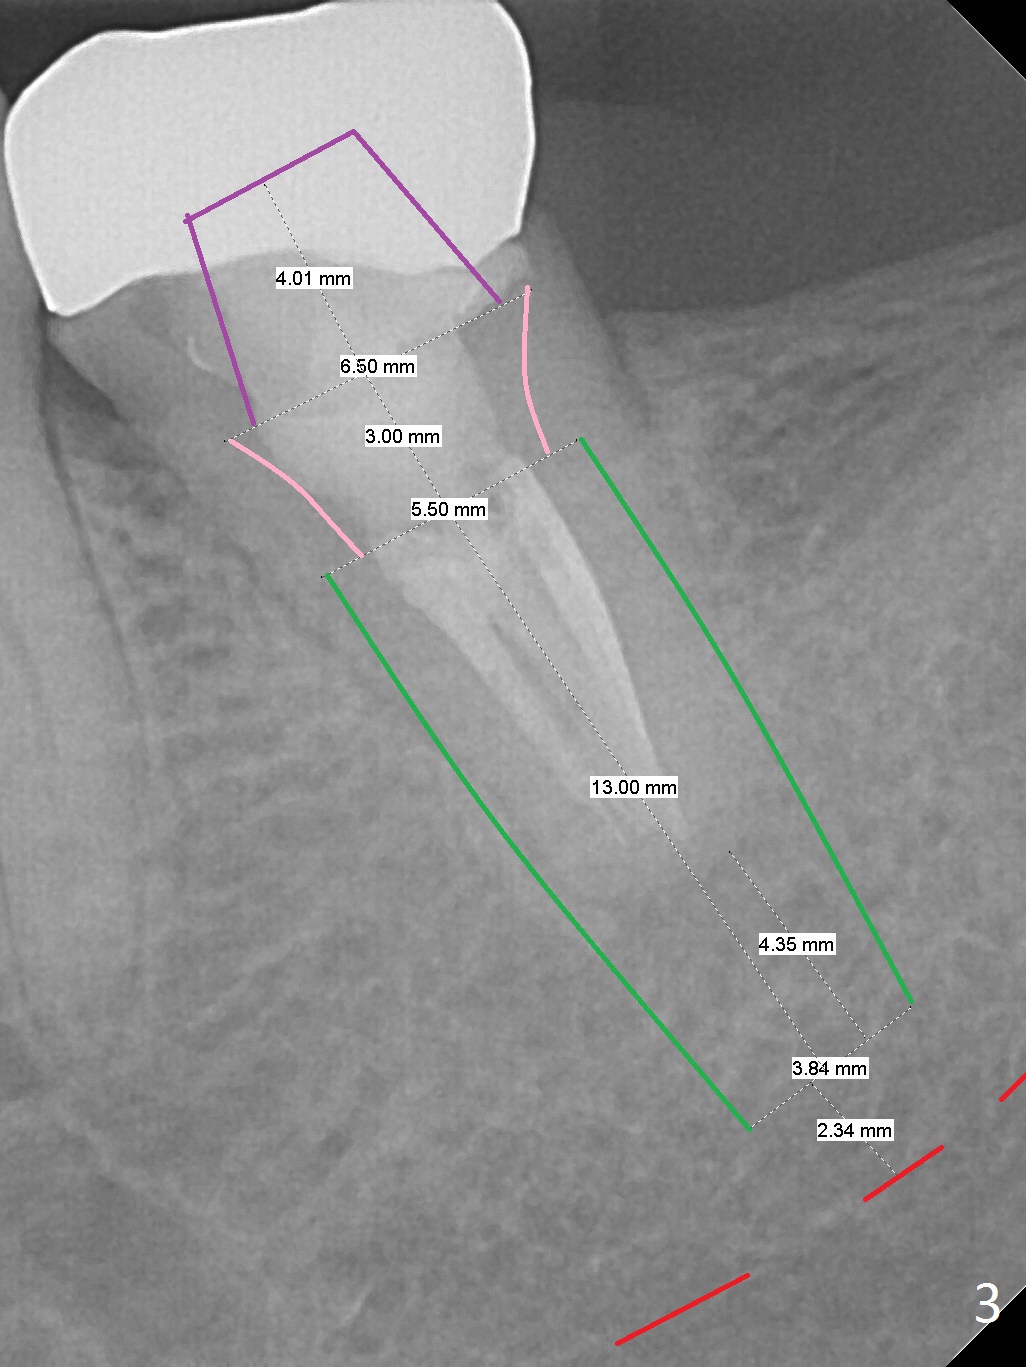

A 45-year-old man has had trouble with the tooth #18 for long time. First, the tooth needed RCT and crown retreatment several years ago (Fig.1). Now there is 2nd caries underneath the crown (Fig.2). After extraction and No Antibiotic, an IBS or Tatum implant will be placed (Fig.3).

Due to limited vertical height, the implant will be placed deep.